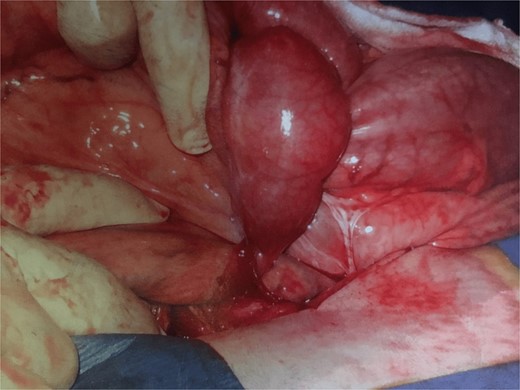

Further exploration revealed a mesenteric adhesive band compressing the herniated bowel and worsening the obstruction (Fig. 1). Approximately 30 cm of necrotic bowel was resected due to ischemia, and blood flow was restored to the remaining bowel (Fig. 2).

Adhesion band with trapped bowel. With permission, www.dssurgery.com.

This image shows the intraoperative view of a mesenteric adhesive bands responsible for the internal hernia. The bands have caused a segment of the small bowel to become trapped, leading to an obstruction of blood flow. The herniated bowel segment is visible, and the mesenteric defect created by the bands can be seen. Surgical manipulation is being used to expose the area.